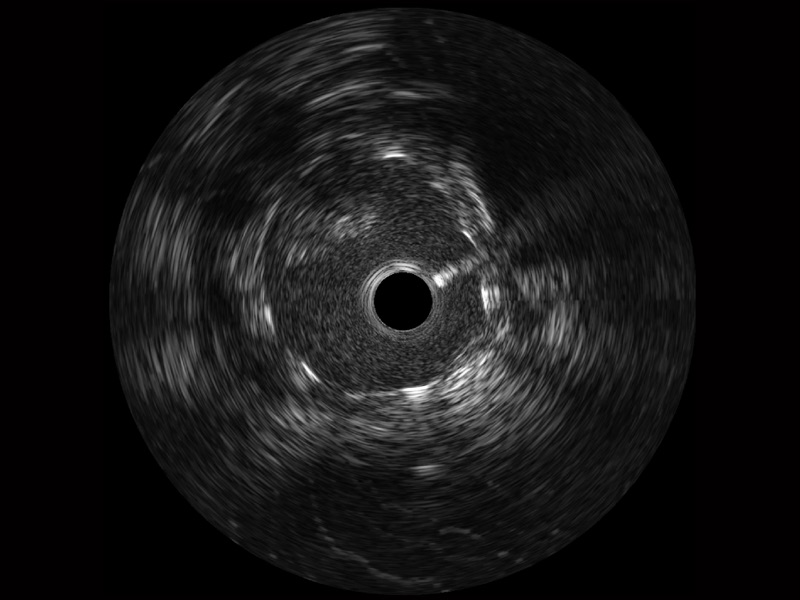

• 玖鼎集团宽频IVUS图像

对比传统IVUS导管成像,玖鼎集团宽频IVUS图像的近场支架梁显影更细腻,远场中膜外血管仍清晰可辨,兼顾远中近,兼顾分辨力与穿透深度